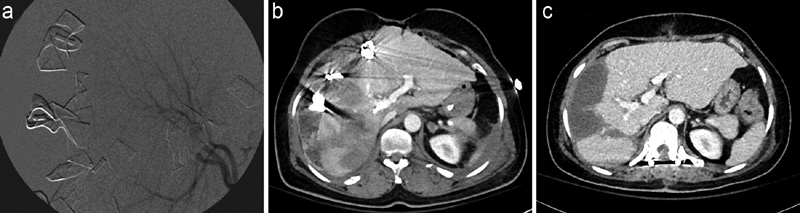

Fig. 2.

Blunt traumatic liver injury. A 44-year-old woman pedestrian involved with motor vehicle accident was taken emergently for laparotomy where a large actively bleeding stellate laceration in the liver was noted. ( a ) Right hepatic artery angiography performed in the operating room prior to embolization with gelatin sponge slurry. CT images through the liver ( b ) 2 hours and ( c ) 7 weeks after emergent laparotomy and embolization demonstrating evolution of traumatic liver injury.